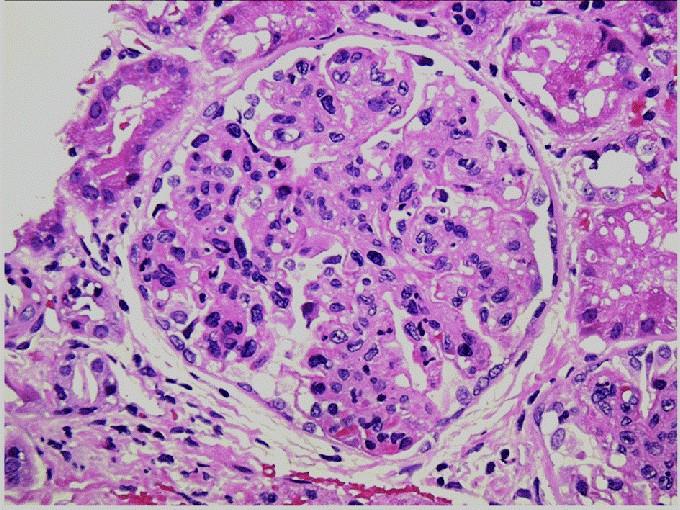

A 65-year-old female presents with a two-week history of fatigue, weight loss, and rapidly worsening renal function. She also reports recent onset of arthralgias and a mild cough. Laboratory studies show elevated creatinine, haematuria, and a 24-hour urine protein of 1.5 grams and positive antiMPO antibodies. A renal biopsy is performed (see representative image). Immunofluorescence demonstrates minimal to no immunoglobulin or complement deposits in the glomeruli. Electron microscopy reveals no significant electron-dense deposits.

Based on these findings, which of the following is the most likely diagnosis?

A. Post-infectious glomerulonephritis

B. Anti-GBM disease

C. IgA nephropathy

D. Pauci-immune ANCA-associated glomerulonephritis

E. Immune complex-mediated membranoproliferative glomerulonephritis

Q7 Explained

■ Correct Answer (D): Pauci-immune ANCA-associated glomerulonephritis is the most likely diagnosis. The clinical picture of RPGN with systemic features (fatigue, weight loss, arthralgias, cough), the minimal immune deposits on IF, absence of electron-dense deposits, and a positive ANCA test (anti-MPO) are all classic findings for this condition.

■ Incorrect Answer (A): Post-infectious glomerulonephritis typically presents with a preceding infection, low C3 complement levels, and granular immune deposits on IF and EM. It does not usually present with systemic features as in this case.

■ Incorrect Answer (B): Anti-GBM disease typically shows linear IgG deposition on IF, and lacks systemic symptoms like arthralgia and cough. Furthermore, the ANCA test would be negative in Anti-GBM disease.

■ Incorrect Answer (C): IgA nephropathy presents with recurrent macroscopic hematuria, and has mesangial IgA deposits on IF, and also typically lacks the systemic features described in this case.

■ Incorrect Answer (E): Immune complex-mediated membranoproliferative glomerulonephritis typically shows granular deposition of IgG and C3 on IF, with deposits on EM, and would also lack the systemic features seen in ANCA-GN. It would also not cause segmental necrosis.